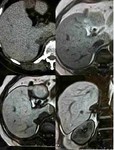

[画像診断]腎腫瘍の「beak sign」について 2010-04-07